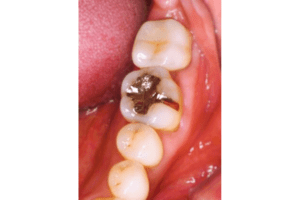

銀歯の中身の写真

麻布十番の歯医者さんで銀歯を外す前の症例写真

こちらは銀歯を外す前と後の写真の比較になります。黒い部分が虫歯になっています。銀歯をつけているとなかなかレントゲンにも虫歯として映ってこないことが多いので、発見が遅れてしまうことがあります。